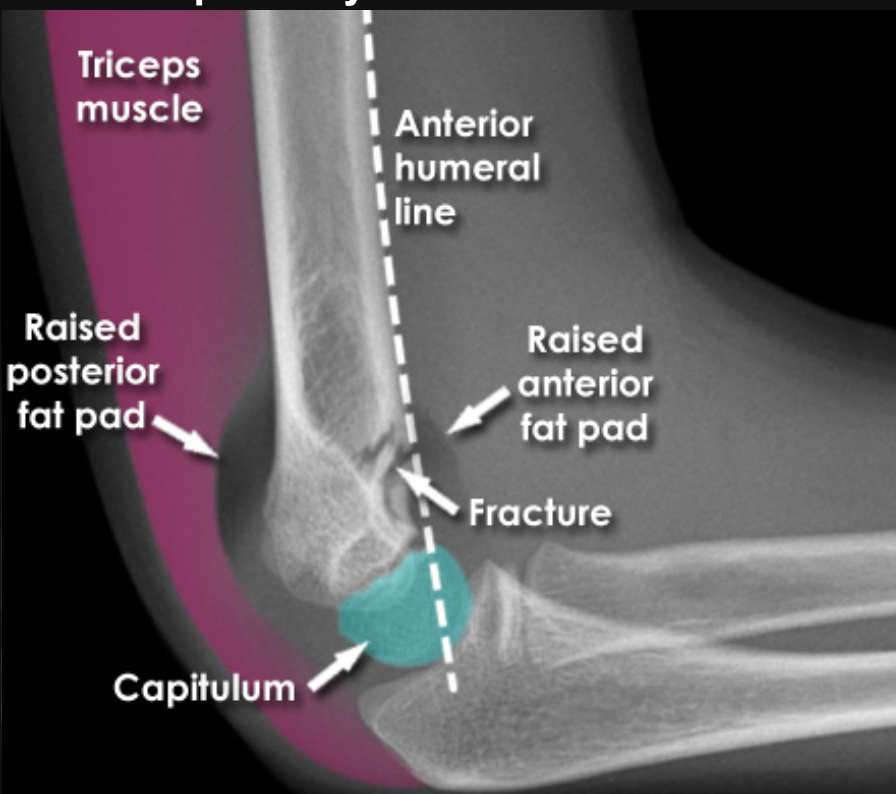

X ray: Plain AP and lateral – sail sign – elevation of anterior fat pad